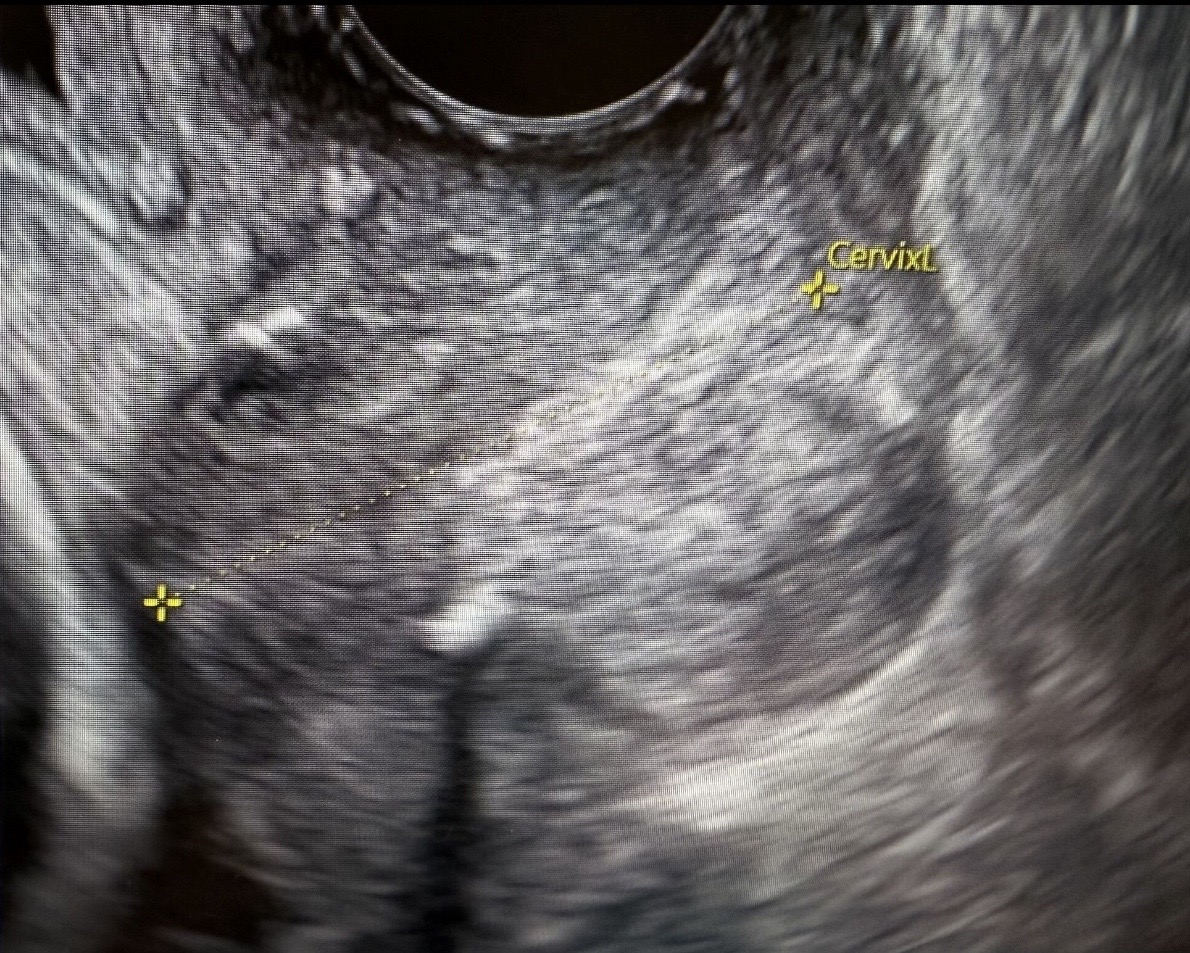

Regular visits to an OBGYN specialist are essential for maintaining reproductive health and addressing any concerns that could impact fertility. These check-ups can help identify and treat any underlying health issues, such as hormonal imbalances or ovarian cyst care, which can affect your ability to conceive.